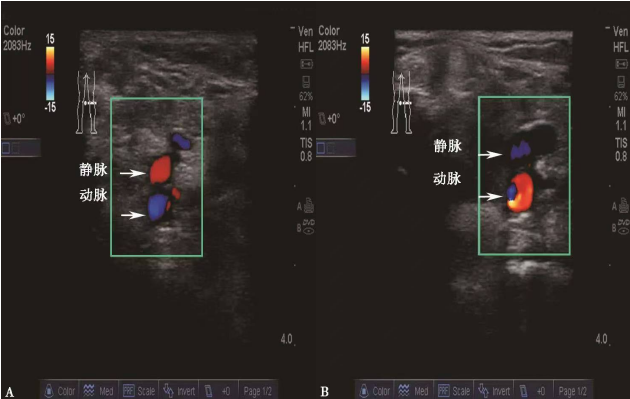

②彩色血流法

找到目标血管后,打开超声的彩色多普勒血流显像时,迎向探头的血流会显示为红色,背离探头的血流显示为蓝色,因此可以结合血管的解剖学基础及超声探头的朝向就可以区分出动静脉。如图A和B均为右侧腘窝处的声像图:图A中探头朝向肢体末端,因此迎向探头的血流(红色)为流回心脏的静脉,而远离探头的血流(蓝色)为流向肢体远端的动脉;图B中的探头方向恰好与A相反,因此红色为动脉,蓝色为静脉。